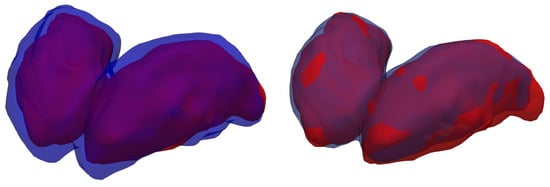

3.6. Qualitative Results

A visualization of the 3D segmentations is used to display the similarities and differences between the ground-truth and each method’s results (Figure 11).

Figure 11.

Thalamus segmentation: ground truth (manual segmentation) in red, silver standard (STAPLE) in blue on the (left), and CNN prediction (with the best model—all input channels combined) in blue on the (right).

When comparing the manual annotation with the silver-standard mask, is is apparent that the latter considers the thalamus a much broader structure than the former. Other studies [7] have observed similar results. Another important consideration is that the segmentation performed by the model after fine-tuning exhibits only minor differences when compared with the specialist’s annotation, with only a few voxels misclassified the borders of the thalami.